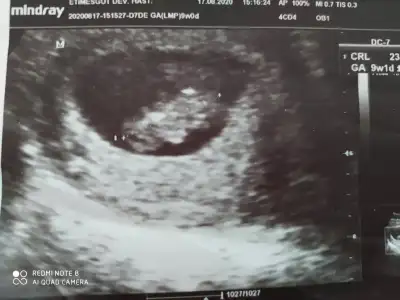

10 ve 9 haftalık fotoğrafları bunlar da 🤗🤗

Eklentiler

• 16009421426447704359213366442684.webp

16009421426447704359213366442684.webp

29,3 KB · Görüntüleme: 51

• 16009421951394688324463703799782.webp

16009421951394688324463703799782.webp

21,4 KB · Görüntüleme: 60